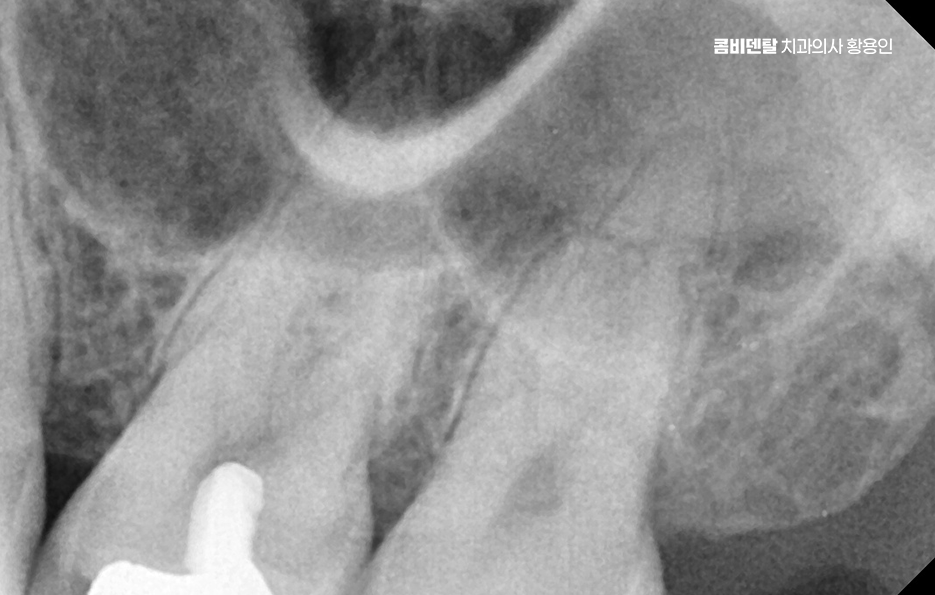

충치가 깊고 넓은 손상이 있을 때는 크라운을 씌우는 게 맞지만, 상대적으로 보존할 수 있는 자연치아가 많고, 신경치료를 동반하지 않아도 되는 상황에서 많이 선택되는 치료가 인레이이며 이렇게 치료 받은 인레이가 치료 직후가 아니라 수년이 지난 후에 인레이 치료 후 통증이 생기는 경우라면, 그 원인은 다양하지만 대체적으로는 보철물 아래쪽에서 발생하는 2차 충치나 인레이와 치아 사이의 미세한 틈, 또는 신경 손상, 잇몸질환으로 인한 문제일 가능성이 높다고 할 수 있어요

인레이 치료 후 통증으로 먼저 가장 흔한 원인 중 하나는 ‘2차 충치’, 즉 인레이 아래에서 새롭게 생긴 충치로 인레이는 정밀하게 본을 떠서 제작되는 맞춤 보철물이지만, 시간이 지나면서 접착제로 붙인 부분이 조금씩 마모되거나 틈이 생길 수 있어요.

이런 틈 사이로 음식물 찌꺼기나 세균이 침투하게 되면 겉으로는 멀쩡해 보여도 안쪽에서부터 충치가 서서히 진행될 수 있는 거예요. 특히 인레이 치료 후 시간이 오래 지났다면, 그 접착제가 녹아서 접합력이 약해졌을 가능성도 있고, 또한 평소 구강 위생 상태가 좋지 않았다면 세균의 공격을 더 많이 받았을 수 있는 거예요.

이런 2차 충치는 인레이로 가려져 있어서 겉으로 보이지 않는 경우가 많고, 증상이 꽤 진행된 이후에야 시림이나 씹을 때의 통증, 잇몸 부위의 묵직한 불편감으로 드러나는 경우가 대부분이다 보니 사실상 증상으로 문제를 인지하는 경우에는 2차 충치가 상당 수준 진행된 경우도 많이 있어요

또 인레이 치료 후 통증이 주로 잇몸 쪽에서 통증이 느껴지는 경우에는 단순히 인레이의 문제가 아니라, 치아 주변의 치주조직에 염증이 생겼을 가능성도 있어요. 인레이 치료 후 오랜 시간이 지났을 때, 특히 위생 관리가 어려운 위치의 치아라면 치석이 쌓이면서 만성 치주염으로 진행될 수 있고 그로 인해 심한 경우에는 잇몸이 내려앉고 치아가 흔들리거나 잇몸에서 통증이 발생하게 되는 거예요.

이런 경우엔 먼저 스케일링이나 잇몸 치료부터 시작해서 통증을 느끼는 지점이 어디인지, 어떤 방식으로 아픈지에 따라 접근 방법이 완전히 달라지기 때문에 임의로 약을 먹기보다는 정확한 진단을 통해 치료 방향을 설정하는 게 우선이라 할 수 있어요

인레이 치료 후 통증 치료는 원인에 따라 다르지만 인레이 치료를 한 해당 부위의 치아 손상이 진행된 경우에는 신경치료와 크라운으로 이어지는 치료가 필요한 경우가 많기 때문에 정기적인 검진과 증상이 있을 때 늦지 않게 대처하는 것이 자연치아 보존에 있어서 중요하며 치주 문제가 병행되었다면 잇몸 치료도 적극적으로 병행해야 자연치아 및 잇몸 건강을 잘 유지할 수 있는 거예요